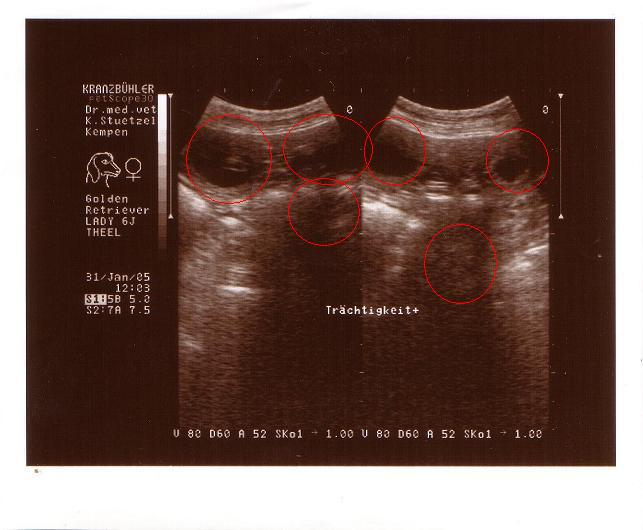

Jetzt ist es gewiss. 31.01.2005

Lady ist trächtig.

Nun heißt es warten und in ca. 5 Wochen liegen

kleine Goldis

im Nest von Marijke Theel